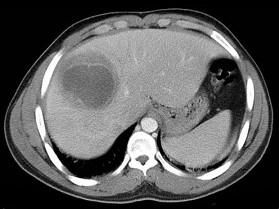

下列图像最佳诊断是什么 ( )A.阿米巴肝脓肿B.原发性肝癌C.肝转移瘤D.肝硬化E.脂肪肝

问题 下列图像最佳诊断是什么 ( )

选项 A.阿米巴肝脓肿 B.原发性肝癌 C.肝转移瘤 D.肝硬化 E.脂肪肝

答案 A